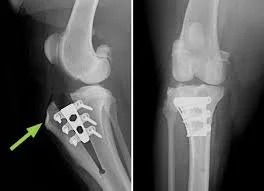

ACL Tear in Dogs: Symptoms, Diagnosis, Surgery, and Recovery

ACL tears are one of the most common orthopedic injuries in dogs and often cause sudden hind leg limping. Learn the symptoms and treatment options for cruciate ligament injuries.

Understanding Ruptured Cranial Cruciate Ligament (CCL) in Dogs

A ruptured cranial cruciate ligament (CCL) is one of the most common and painful knee injuries in dogs. This in‑depth guide explains what causes CCL tears, how to recognize the signs, the pros and cons of each surgical option, what recovery looks like, and how to support long‑term joint health. Whether your dog has a sudden limp or chronic stiffness, this article helps you understand the condition and make informed decisions about treatment.